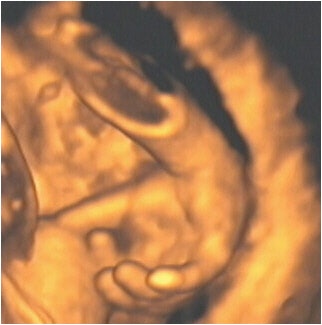

![]() |

| Figure 8, a 3-D ultrasound image of a fetus with hands in front of face at 21 weeks gestation. Image courtesy of Stefano Ciatti, M.D. |